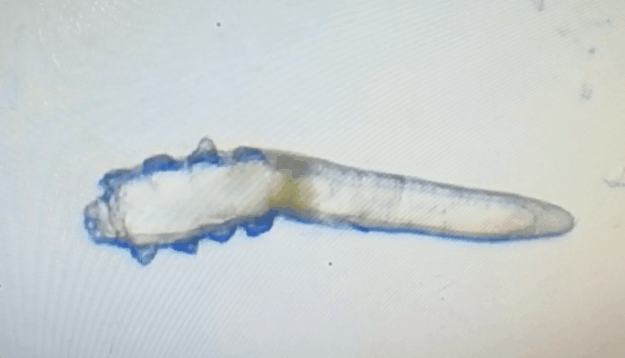

林女士是一家公司的白領(lǐng),常常需要濃妝出席各種會議,然而光鮮亮麗的背后,林女士的眼睛正遭受著和陳先生同樣的癥狀。在螨蟲鏡檢中,當(dāng)看到自己的睫毛上爬滿了十幾只透明的生物-螨蟲,林女士嚇了一跳。幸而,經(jīng)過廈門眼科中心干眼中心的治療,林女士解決了多年的眼睛干癢問題。

這就不得不提到眼科醫(yī)生經(jīng)常使用的螨蟲檢測工具——螨蟲鏡檢。它通過顯微利器,無死角全方位掃描你的睫毛,讓螨蟲無處遁形。